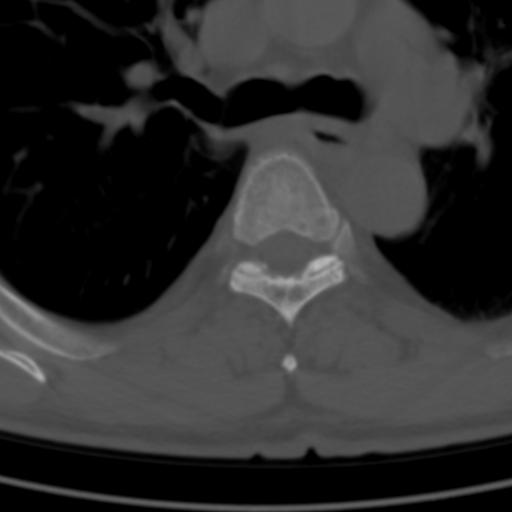

标题: CT25189:胸椎ct,请会诊!

既往食管癌,现行ct检查!

仅见椎体退行性改变

中上段食道癌,椎体轻度退变。

椎体退行性改变,食管癌。

支持中上段食道癌,椎体轻度退变,必要时做ect。

支持中上段食道癌,椎体轻度退变。